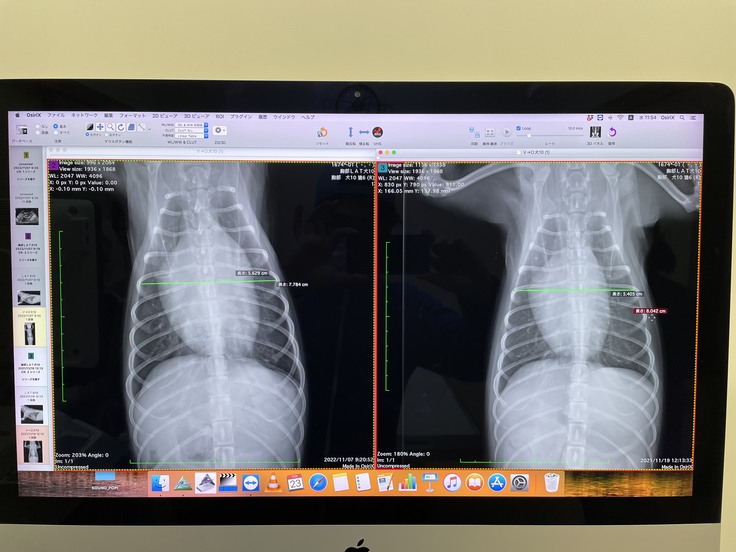

うーちゃんの心臓です。それぞれ右に比べて左の画像の心臓が肥大していて、これも症状の進行の影響だと主治医の先生より説明を受けました。